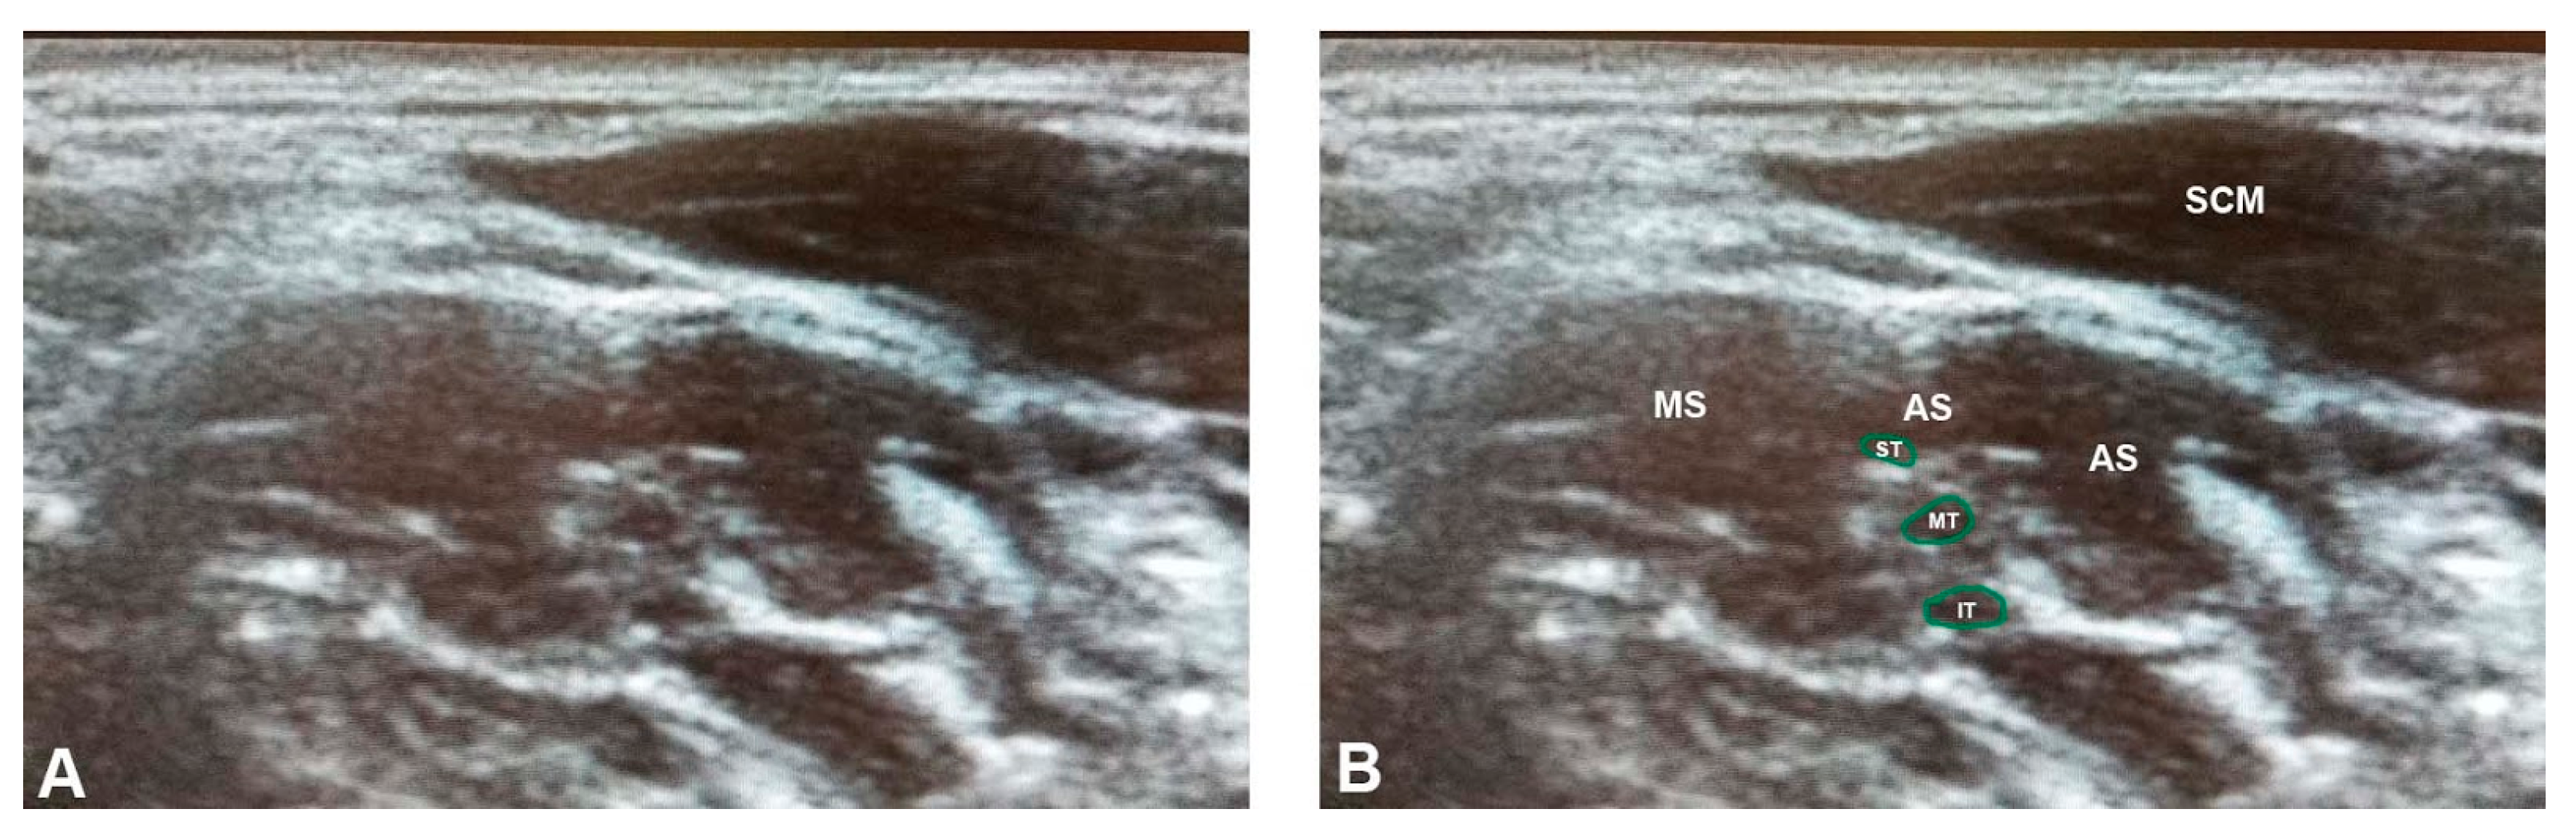

3.2. Ultrasonographic Results